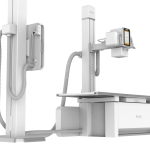

DMXR09 Medical High Frequency Radiography System Digital Stationary DR X ray Machine Scanner prices

Model: PSKU0136

1. Features:1) Input power: 380VAC, three phase2) Nominal electric power: 50kW3) Inverter frequency: Max: 300kHz4) Tube voltage range: 40~150kV5) Current output range: 10~630mA6) Time of exposure: 1ms~10000ms7) Current & Time ra...

| Product Name | DMXR09 Medical High Frequency Radiography System Digital Stationary DR X ray Machine Scanner prices |

| SKU | PSKU0136 |

| Size | 2120*965*450-740mm |

| Packing Size of set | 2090*1100*430mm (1 set per carton) |

| Loading capacity | 250kg / 551lbs |

1. Features:

1) Input power: 380VAC, three phase

2) Nominal electric power: 50kW

3) Inverter frequency: Max: 300kHz

4) Tube voltage range: 40~150kV

5) Current output range: 10~630mA

6) Time of exposure: 1ms~10000ms

7) Current & Time range: 0.4~1000mAs

8) Automatic APR linkage function: Provide

9) Focal spot: 0.6/1.2mm

10) Focal power: 20kW/50kW

11) Tube voltage range: 40~150kV

12) Anode heat capacity: 300kHU

13) Rotary anode: 2800 RPM